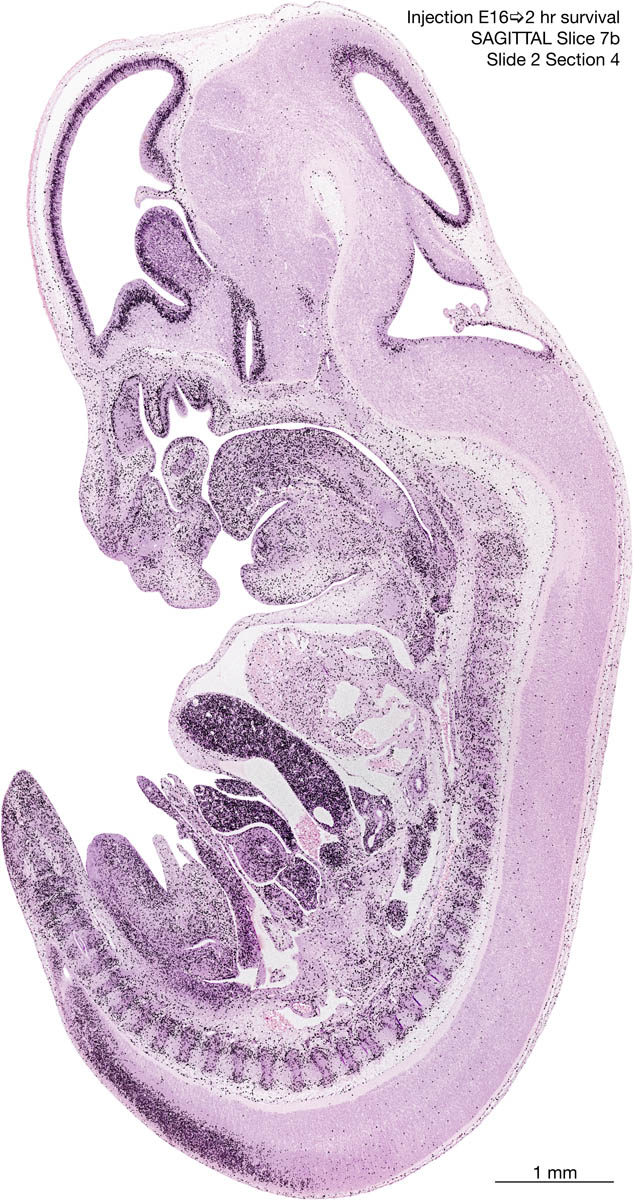

E16 2hr Survival Archived Images-Sagittal The following images are from a paraffin-embedded sagittally-sectioned E16 rat embryo exposed to tritiated thymidine 2 hours before death. Download: Large | High Res Download: Large | High Res Download: Large | High Res Download: Large | High Res Download: Large | High Res Download: Large | High Res Download: Large | High Res Download: Large | High Res Download: Large | High Res Download: Large | High Res Download: Large | High Res Download: Large | High Res Download: Large | High Res Download: Large | High Res Download: Large | High Res Download: Large | High Res Download: Large | High Res Download: Large | High Res Download: Large | High Res Download: Large | High Res Download: Large | High Res Download: Large | High Res Download: Large | High Res Download: Large | High Res Download: Large | High Res Download: Large | High Res Download: Large | High Res Download: Large | High Res Download: Large | High Res Download: Large | High Res Download: Large | High Res Download: Large | High Res Download: Large | High Res